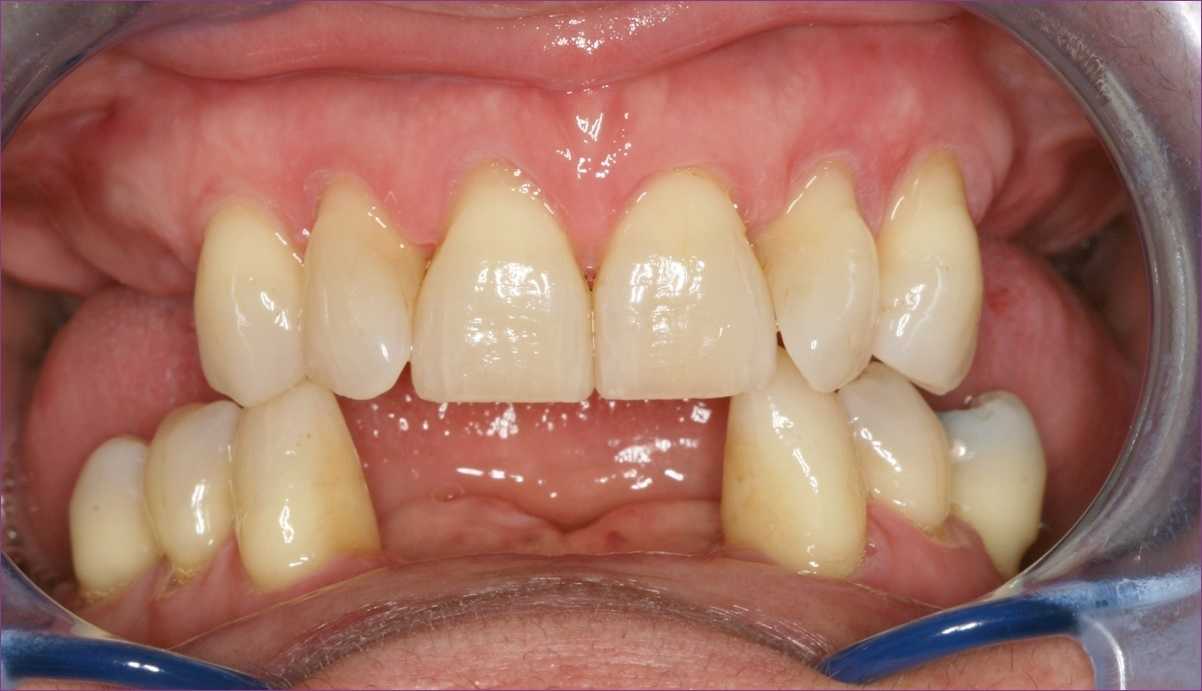

Középkorú nőpáciensünk azzal a panasszal kereste fel fogászatunkat, hogy meglévő fogai mozognak. A szájvizsgálat és a panoráma-röntgenfelvétel alapján egyértelművé vált, hogy a tünetek hátterében előrehaladott fogágybetegség áll.

Sajnálatos módon számos fog ugyan épnek volt mondható, ám a nagyfokú csontpusztulás miatt el kellett távolítani őket.

A kezelési terv készítése során fontos szempont volt, hogy a páciens ne maradjon fog nélkül. A menthetetlen fogak eltávolítását megelőzően ideiglenes fogpótlásokat készítettünk a fogtechnikai labor segítségével, és a foghúzásokat követően ezeket egyből meg is kapta a páciens.